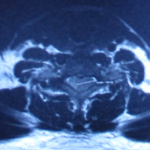

After detailed questioning, it is obvious that Mr. Lin’s problem has caused cauda equina syndrome. There may be a tumor in the spinal cord or a severe lumbar disc herniation compressing the spinal cord. Immediately arrange the patient to take a full spine MRI, and immediately after 2 hours after reading the scans, it turned out that the patient had a 1.6cm tumor at the 6/7 spinal canal position of the cervical spine and severely compressed the spinal cord. He was immediately referred to a neurosurgeon on the same day and arranged to be admitted to the hospital that night, and the cervical cord tumor was removed the next day by surgery. After the operation, the patient’s foot pain and numbness gradually improved.